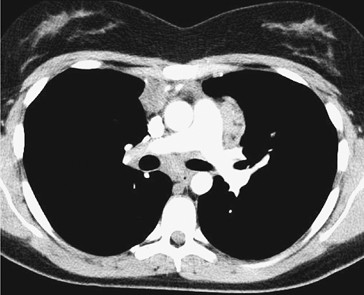

| Klinik: schmerzlose Lymphknoten (zervikal, mediastinal) B-Symptome (Fieber, Nachtschweiß, Gewichtsverlust) Pruritus, evtl. Alkoholschmerz | Klinik: Lymphknoten + extranodal (GI, Haut, ZNS) B-Symptome variabel |

| Stadien: Ann-Arbor (I–IV) + Risikofaktoren | Wichtige Subtypen: indolent: Follikuläres Lymphom (oft „watch & wait“) aggressiv: Diffus großzelliges B-Zell-Lymphom |

- Disseminierte Organbeteiligung (Leber, KM, Lunge etc.)